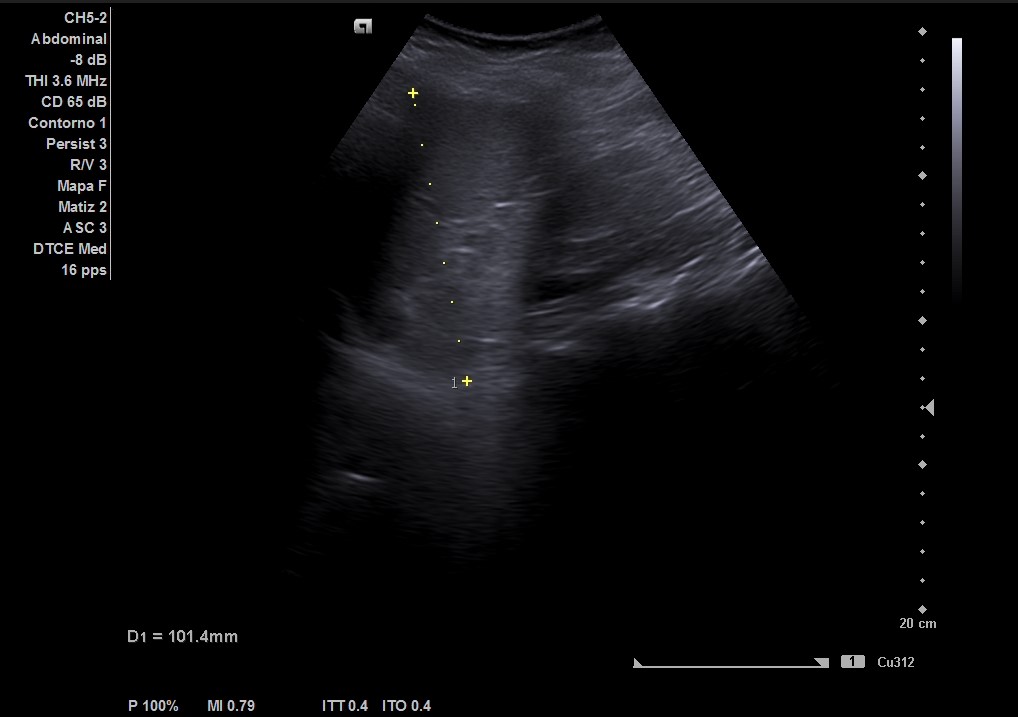

Ecografía abdominal: masa heterogénea de 10 x 10 cm dependiente de útero con vascularización periférica. No se observa la vejiga al estar repleccionada y desplazada por dicha masa. Se vuelve a hacer ecografía con vejiga llena y se observa cómo deforma la pared por efecto masa. Vejiga sin litiasis en su interior, no globo vesical.

La paciente es valorada en consulta de patología ginecológica. Le realizan una ecografía abdominal y transvaginal que describe: útero de unos 13 cm de histerectomía. Presenta varios miomas intramurales, destacando uno en cara posterior de 110 x 102 mm que parece contactar con cavidad endometrial sin desplazarla.